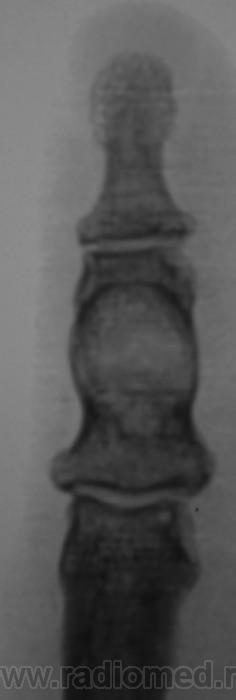

"Пальчик"...

Аневризматическая костная киста. Жалобы есть?

Энхондрома

Туберкулёзный остит средней фаланги 2 пальца.

В дифф.ряд-spina ventosa tuberculosa.

Да 100- пудово, какие ТБС! Схожие картинки - не критерии, обращаю внимание наличие хоть каких деструкций при ТВС, хоть чего нибудь!

Это точно не туберкулез. Очень точно.А на кисту вот похоже.

А вот здесь очень близко к костной кисте. Увеличение объема (вздутие), тонкий ободок (стенка) с четкими контурами, содержимое однородное. Даже дифряд строить не хочется.